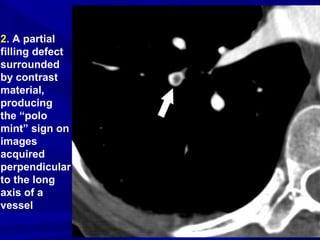

2. A partial

filling defect

surrounded

by contrast

material,

producing

the “polo

mint” sign on

images

acquired

perpendicular

to the long

axis of a

vessel